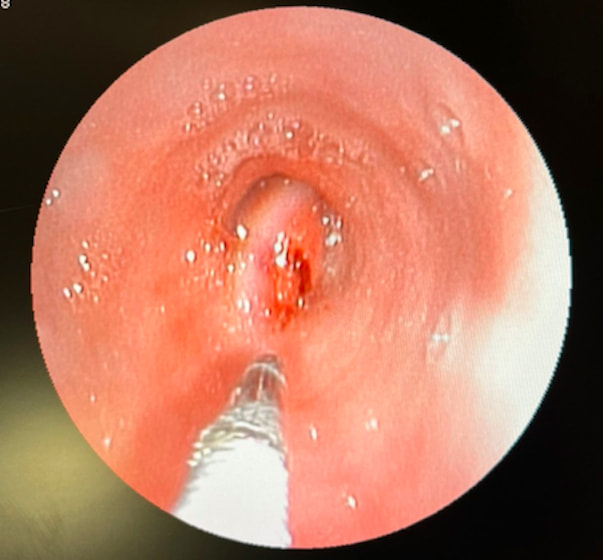

膀胱腫瘤(2025/11/25)

犬猫共に、膀胱内に腫瘤が発生することがあり、その場合には排尿しづらそうな様子や、血尿、頻尿といった、膀胱炎などと同様の症状がよく認められます。超音波検査を行うことで、膀胱内に腫瘤が形成されているかどうかを確認することが出来ます。また、カテーテルを用いて採材を行い、細胞診検査や遺伝子検査を行うことで診断を行います。診断後、腫瘤の発生状況などにより、外科的/内科的治療を検討していきます。膀胱内腫瘤を認めた場合には悪性腫瘍であることが比較的多いこともあり、普段と異なる排尿の様子が認められた場合などは、お早めにご相談下さい。

獣医師 池田